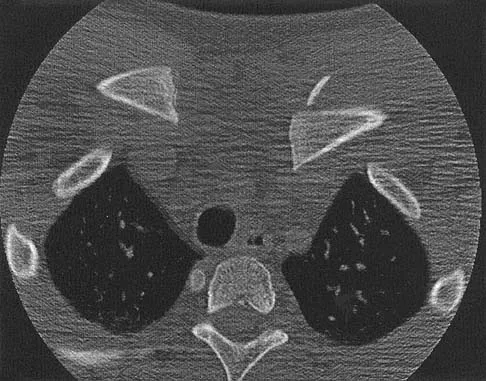

Question 32

A 13-year-old boy has a mild deformity of the left sternoclavicular joint after being involved in a rollover accident while riding an all-terrain vehicle. Examination in the emergency department reveals that he is hemodynamically stable, and his neurovascular examination is normal. The CT scan shown in Figure 22 was obtained because radiographs were inconclusive. Management should consist of

Explanation